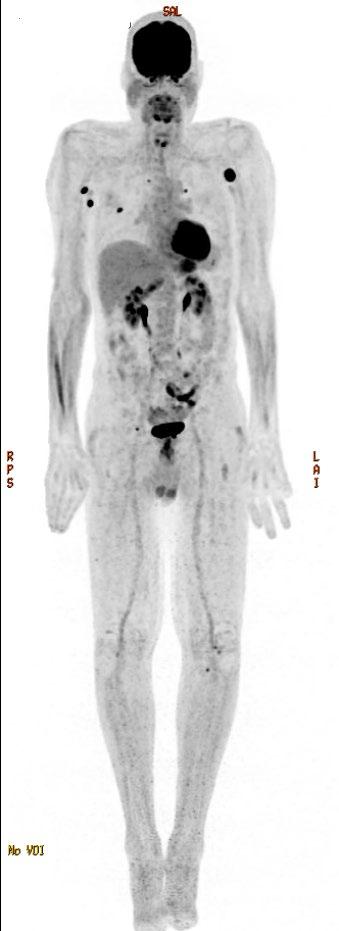

• Imaging may be needed depending on type and location of pain (eg, MRI, PET-CT)